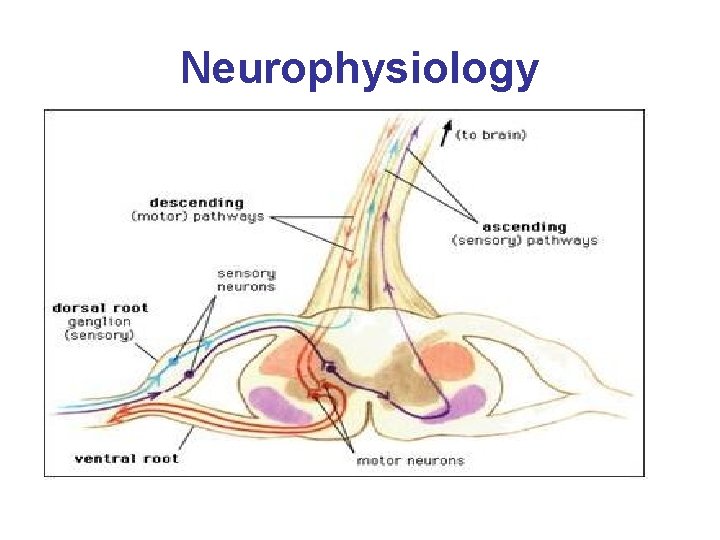

Neurophysiology • Local Anesthesia (LA) blocks transmission in ascending and descending nerve pathways. The order of the nerve fibers affected by LA is sensory, motor, and sympathetic. • Of note, resolution or regression of the block occurs first in motor fibers, then sensory and lastly sympathetic. • This pattern is important when instructing patients about preemptive pain management and postoperative use of the extremity.

Neurophysiology

Neurophysiology • On a cellular level, it is the influx of sodium into the cell that is responsible for generating an action potential causing depolarization and conduction of the nerve fibers. • Local Anesthetic (LA) changes the permeability of the cell membrane to sodium interfering with the ability of sodium to enter the cell. This interference with nerve fiber conduction prevents the sensory or motor information from being transmitted to and from the brain. This also applies to cardiac conduction.